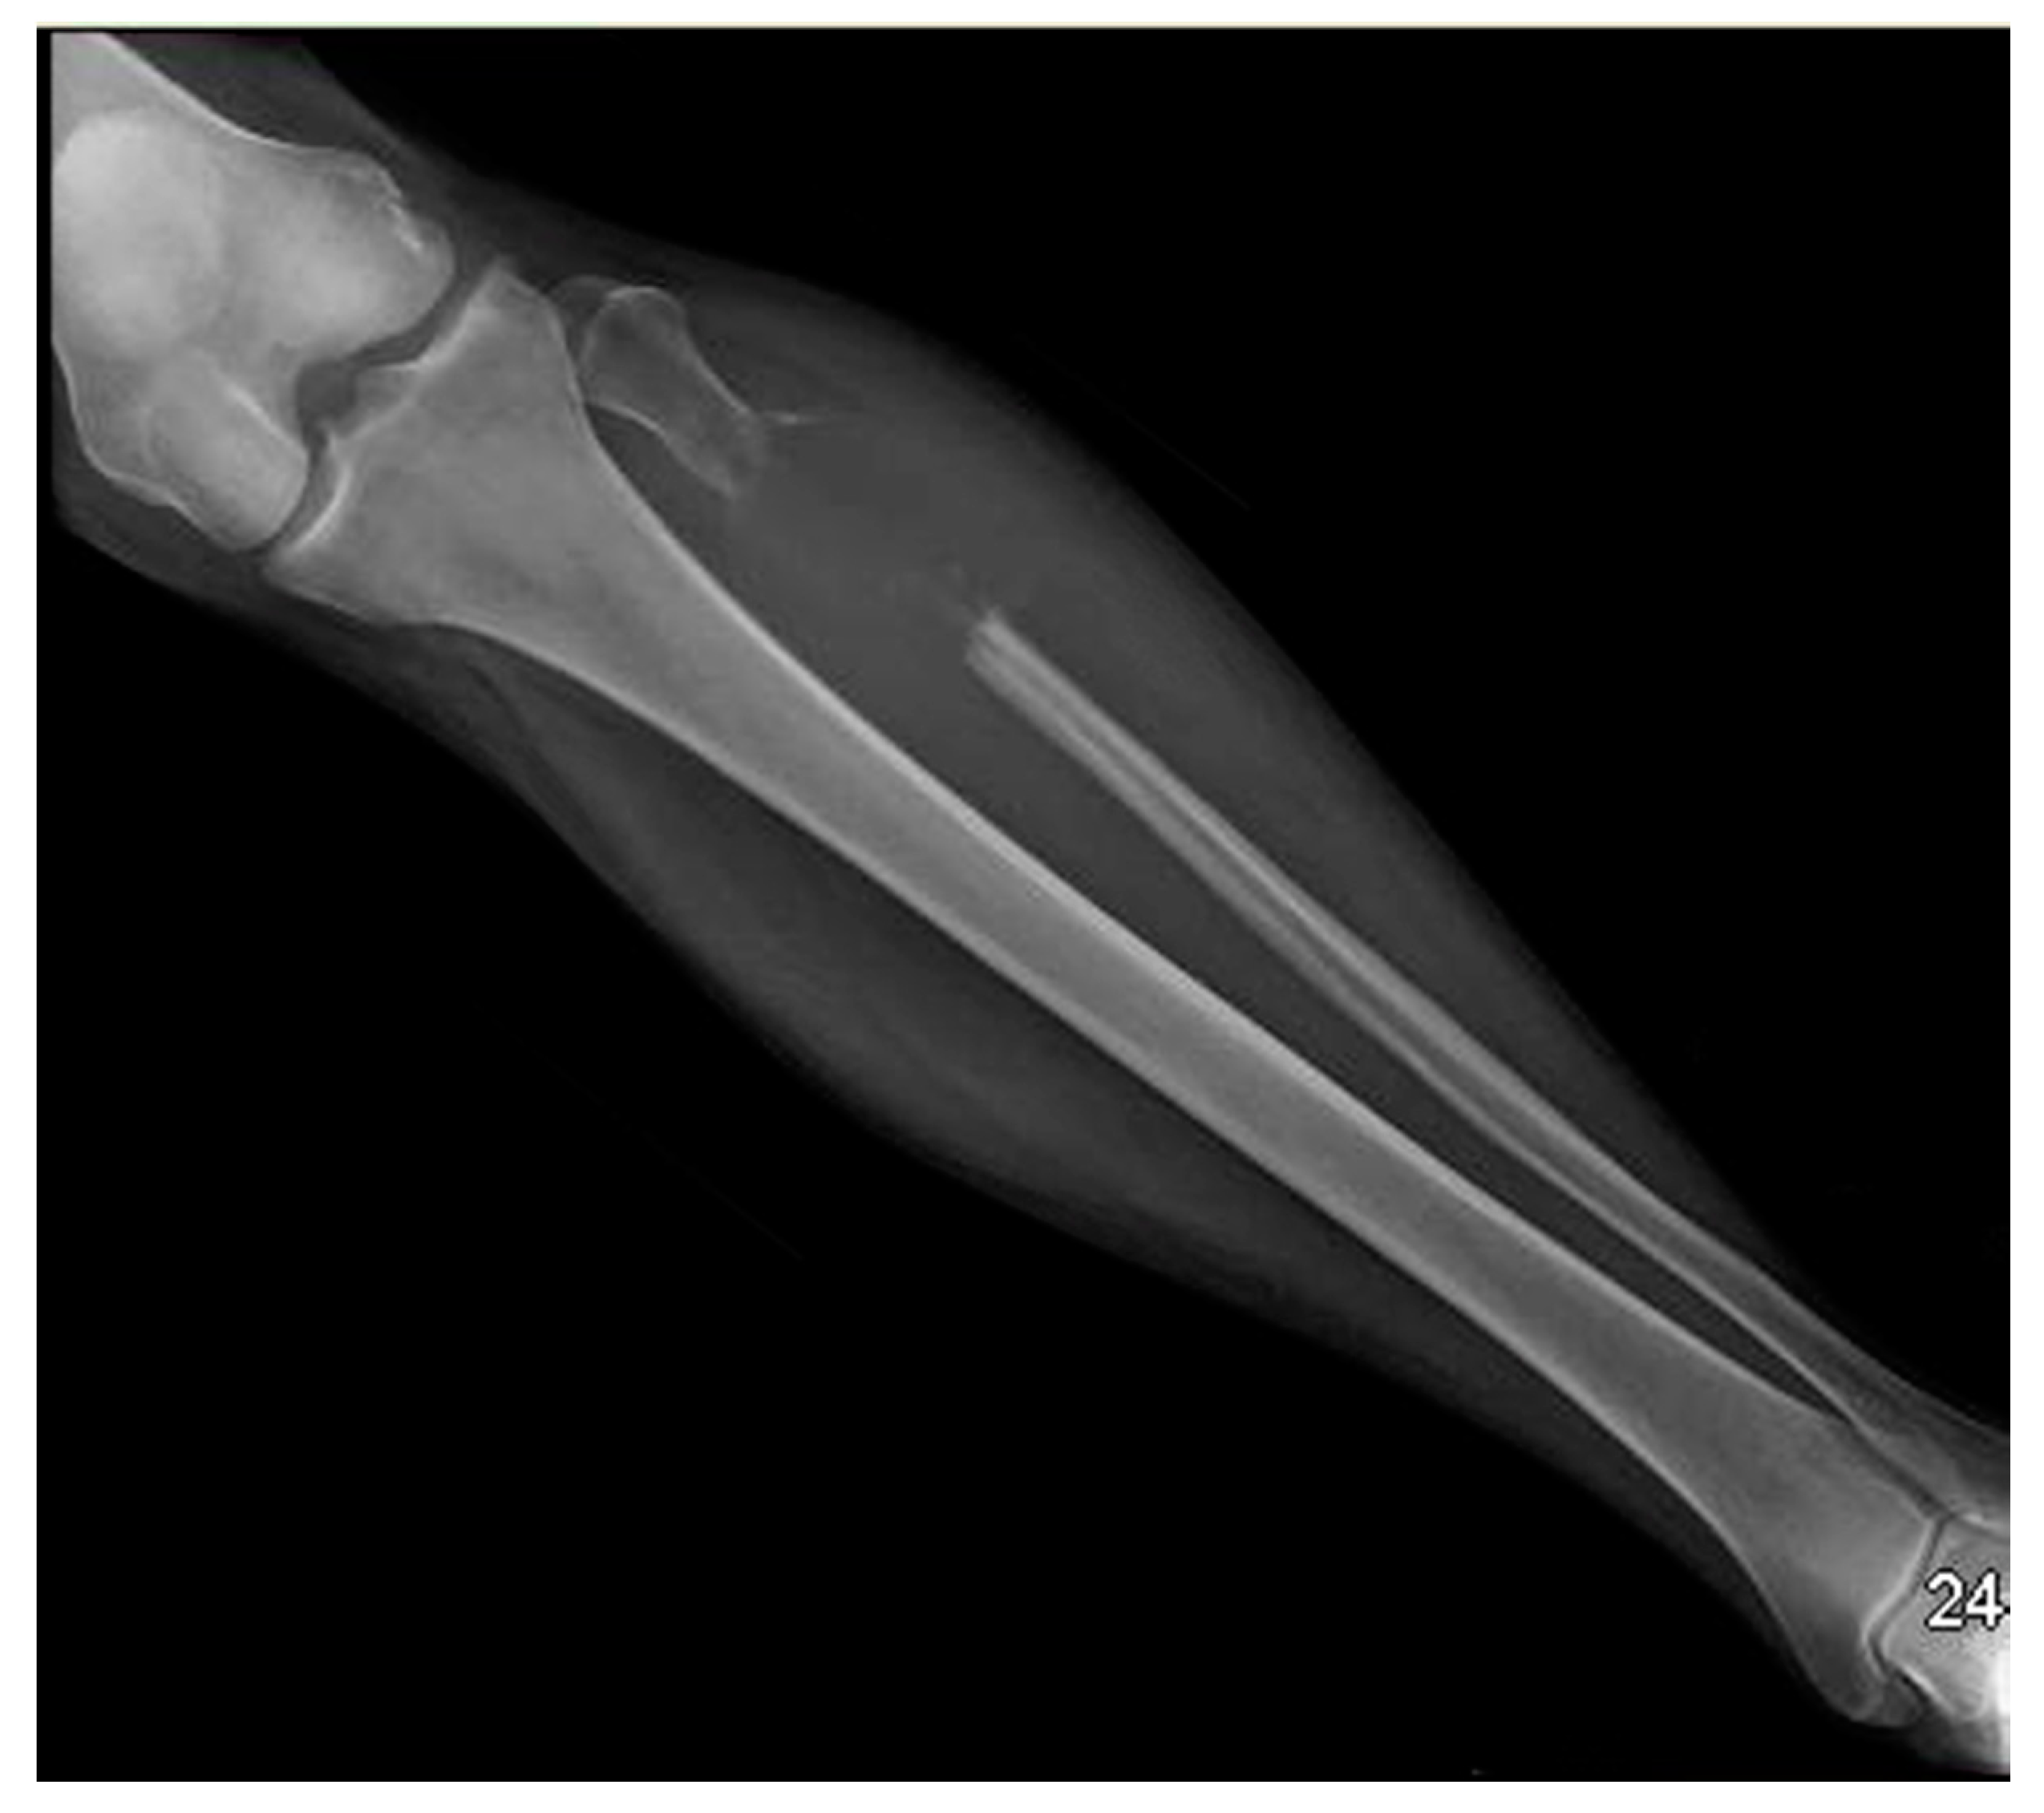

2. Case Presentation